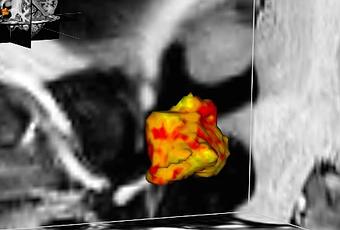

Chez ces patientes dépressives, les zones de l'hypothalamus (en rouge sur visuel) sont plus développées que chez leurs homologues en bonne santé. Les chercheurs suggèrent que cette « hypertrophie » pouvait résulter soit d’une prédisposition, soit de l’exposition à des facteurs de stress environnementaux. On savait déjà sait que les personnes plus prédisposées à la dépression présentent un dérèglement du système de réponse au stress endogène ou axe hypothalamo-hypophyso-surrénalien (axe HPA), qui est normalement déclenché en cas de situation stressante. Cette réponse augmente les niveaux de cortisol, fournissant au corps plus d'énergie lorsqu'il est confronté à une menace ou à un défi. Une fois la situation difficile passée, plusieurs mécanismes de contrôle de l'axe HPA garantissent normalement un retour à l'équilibre du système.

- l'hypothalamus gauche est en moyenne de 5% supérieur chez les patients dépressifs vs leurs homologues en bonne santé ;